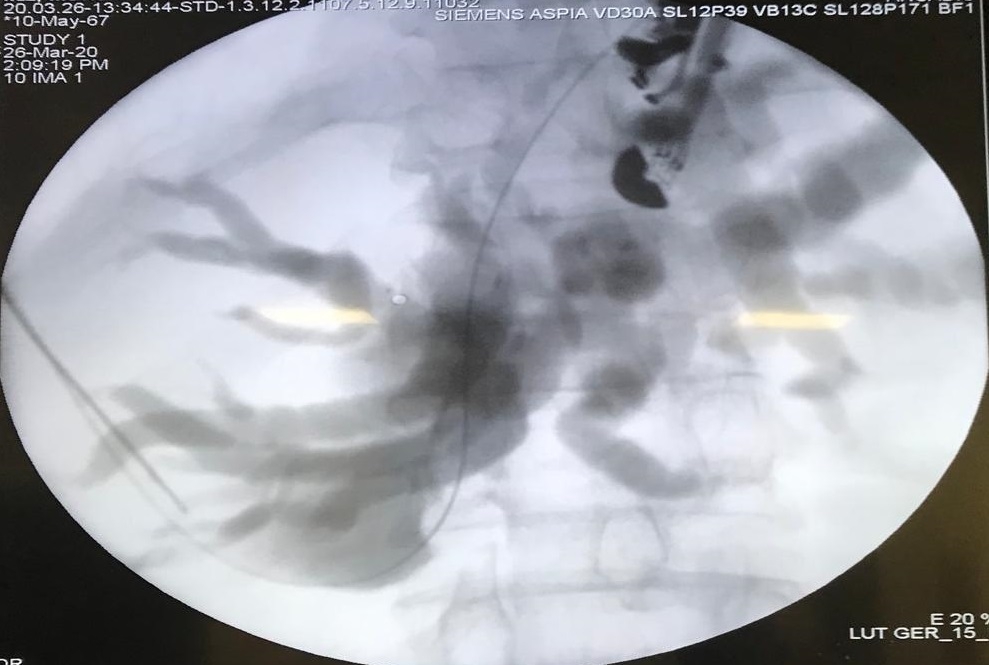

16 Nisan 2020 Perşembe 20:55Ancak Düzce Üniversitesi Hastanesi’nde yapılan değerlendirme sonrası dünyada yeni bir yöntem olan Endoskopik Ultrasonografi ile hastanın ince barsaklarından karaciğerine bir iğne yardımı ile girilip, safranın karaciğerden ince barsağa bir stent vasıtasıyla akıtılabileceği belirlendi. İç Hastalıkları Anabilim Dalı ve Gastroenteroloji Bilim Dalı Öğretim Üyesi Doç. Dr. Serkan Torun ve Genel Cerrahi Anabilim Dalı’ndan Dr. Öğr. Üyesi Mehmet Fuat Çetin, hasta ve hasta yakınlarının ortak kararı ile 54 yaşındaki hastaya Hibrid EUS-ERCP işlemini başarıyla gerçekleştirdi.